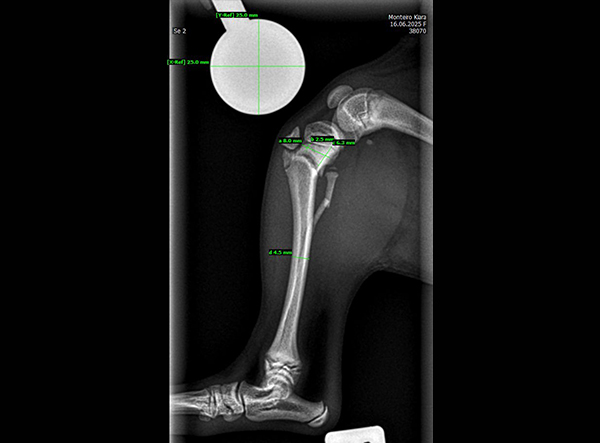

The patient, an 18-week-old female Yorkshire Terrier, was referred for surgery on October 21, 2025. The dog had sustained a fall from the owner’s arms, resulting in a fracture of the proximal tibial metaphysis just below the growth plate, along with a fibular fracture. Given the patient’s very small size and young age, precise anatomical fixation and minimal disruption of the growth zone were essential.

An open reduction and internal fixation (ORIF) was performed via a medial approach to the proximal tibia.Implant Used: 1.5 mm LeiLOX TPLO Swing Titanium Plate

The surgery was completed without complications. Postoperative radiographs confirmed anatomical alignment and stable fixation. With careful rehabilitation, the young Yorkshire Terrier is expected to regain full function and resume normal activity pain-free.